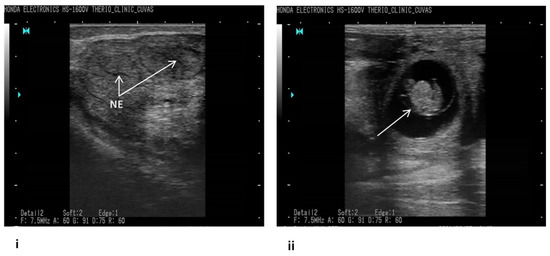

2.1. Tracking Bovine Endometritis

- Fissore, R.A.; Edmondson, A.J.; Pashen, R.L.; Bondurant, R.H. The use of ultrasonography for the study of the bovine reproductive tract. II. Non-pregnant, pregnant and pathological conditions of the uterus. Anim. Reprod. Sci. 1986, 12, 167–177. [Google Scholar] [CrossRef]

- Pierson, R.A.; Ginther, O.J. Ultrasonic imaging of the ovaries and uterus in cattle. Theriogenology 1988, 29, 21–37. [Google Scholar] [CrossRef]

- Ihnatsenka, B.; Boezaart, A.P. Ultrasound: Basic understanding and learning the language. Int. J. Shoulder Surg. 2010, 4, 55. [Google Scholar]